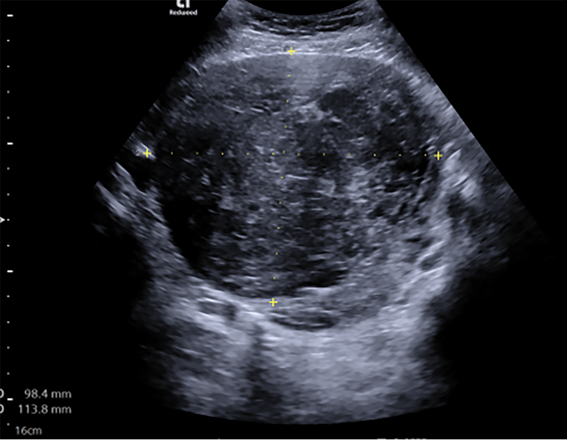

Atlikus ginekologinę apžiūrą nustatyta, kad gimda palpuojant padidėjusi ir nelygi, gimdos priedai atskirai neišpalpuoti. Transvaginalinio ultragarsinio tyrimo metu gimdos kūno projekcijoje rastas didelių matmenų mišrios echostruktūros darinys, turintis kraujotaką. Darinio dydis ‒ 9,84×11,38 cm. Gimda ir kiaušidės atskirai nevizualizuotos, laisvo skysčio ar papildomų darinių mažajame dubenyje nenustatyta (1 ir 2 pav.).

1 pav. Transvaginalinio ultragarsinio tyrimo metu gimdoje rastas mišrios echostruktūros darinys